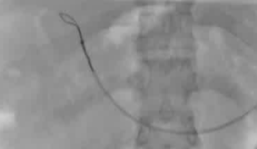

该程序包含以下步骤: 经脾脏入路:在超声引导下,刺穿脾静脉内的一个实质内分支。 在通过脾静脉造影确认了静脉通路后,导管和导丝被推进,以穿过脾静脉并抵达血栓化的门静脉。在门静脉/右门静脉分支处放置圈套器,为TIPS穿刺精准定位。TIPS穿刺圈套器,并穿过圈套器完成TIPS

步骤: 鉴于慢性血栓形成的复杂性: 一种经脾脏途径的门静脉再通术(PVR)。 随后是经颈静脉肝内门体分流术 。